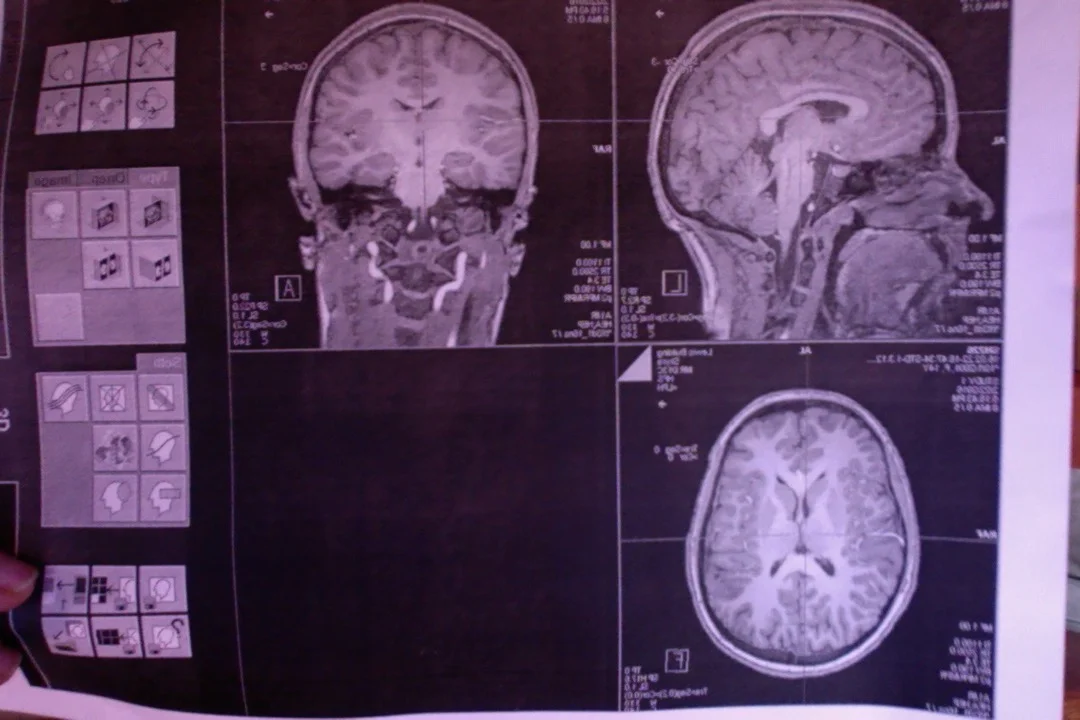

the beautiful brain

March 7, 2016

My daughter is currently participating in a study that requested she do an MRI scan.  When I picked her up from the UO lab last week she handed me this photocopy.  It made me a little whoozy and substantially awed, like starring through the lense of a powerfultelescope aimed at some vast unreachable spanse of stellar bodies.  I can't read these pictures in any real data collection terms.  I don't speak brain anatomy, but I am an artist, and the patterns, pathways, and beautiful symmetry of these images stun me.  Like I am just now meeting a hidden part of this human being I so love and admire.